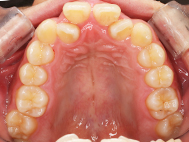

Before

| 症状 | 上顎前歯部叢生 |

上の前歯がハの字隣の歯が引っ込んでいる

前歯のガタガタが気になるとの事で来院されました。

装着が目立ちたくないとの事でアライナ-での矯正を希望されました、歯の間を削り少し歯の幅をスリムにして綺麗なアーチに並びました。